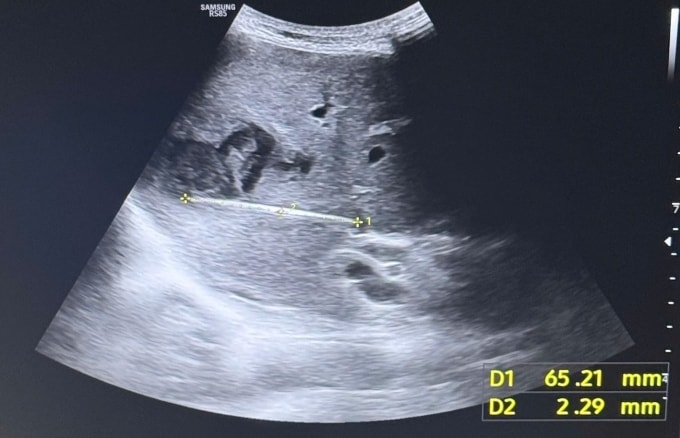

Ngày 4/2, bác sĩ Trần Đình Quốc, Khoa Ngoại Gan Mật Tụy, Bệnh viện Chợ Rẫy, cho biết bệnh nhân nhập viện trong tình trạng sốt kéo dài không rõ nguyên nhân, đau vùng thượng vị và hạ sườn phải, sau khi điều trị nhiều nơi không hiệu quả. Siêu âm và CT bụng phát hiện dị vật cản quang dài 6-7 cm nằm trọn trong gan, xung quanh hình thành ổ áp xe.

Bác sĩ Mã Phước Nguyên, Phó trưởng Khoa Nội Tiêu Hóa, nhận định đây là trường hợp khó chẩn đoán ở tuyến dưới vì triệu chứng lâm sàng giống áp xe gan đơn thuần. Hình ảnh siêu âm thông thường khó phát hiện vết xuyên thành dạ dày. Dị vật này đã xuyên thủng thành ống tiêu hóa, di chuyển âm thầm và khu trú sâu trong gan.